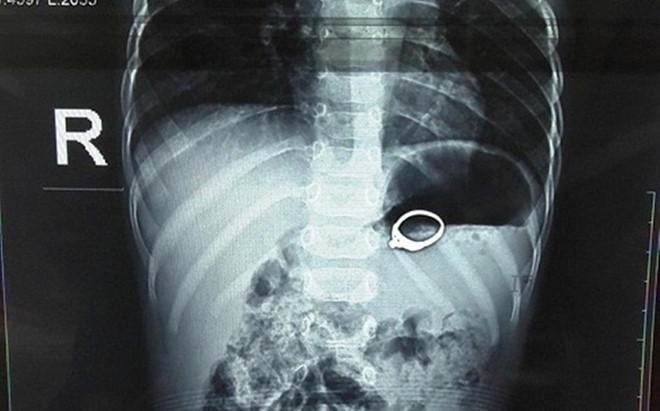

Chiếc nhẫn trong dạ dày cháu Đ. (ảnh: Bệnh viện cung cấp)

Theo đó, trong lúc chơi đùa, cháu Đ. đã ngậm chiếc nhẫn rồi nuốt vào bụng. Sau khi vào viện, bệnh nhi được chỉ định can thiệp loại bỏ di vật. Chiếc nhẫn được lấy ra sau đó, sức khỏe cháu Đ. vẫn ổn định.